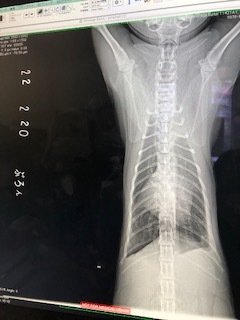

・レントゲン検査

肺も白い部分は変化ありませんでした。